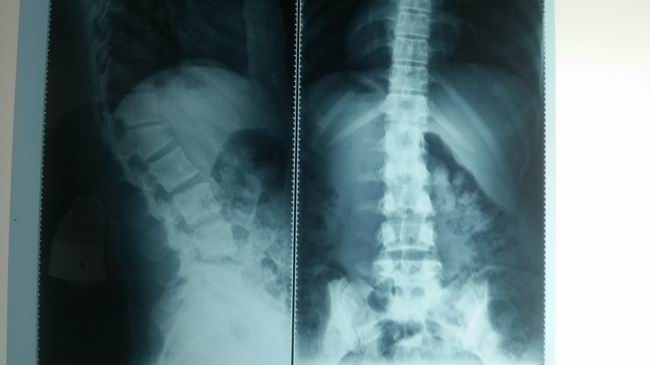

腰椎压缩性骨折治疗前

一、胸腰椎压缩骨折治疗组

本器材的原理:通过患者胸锁骨与耻骨联合处为支撑力点,用《可调式固定支具(腰椎型)》中提拉装置,提升腰部后面的固定带。把契形骨折通过腰部固定带直接提拉出正常范围内腰部的生理弧度。使胸腰椎契形状骨折,逐步改变弧度,从而使骨折部位复位。一般骨折二周内可以逐步通过提拉装置,每隔三天提拉一次,直至坐稳弧度在正常范围内为止。